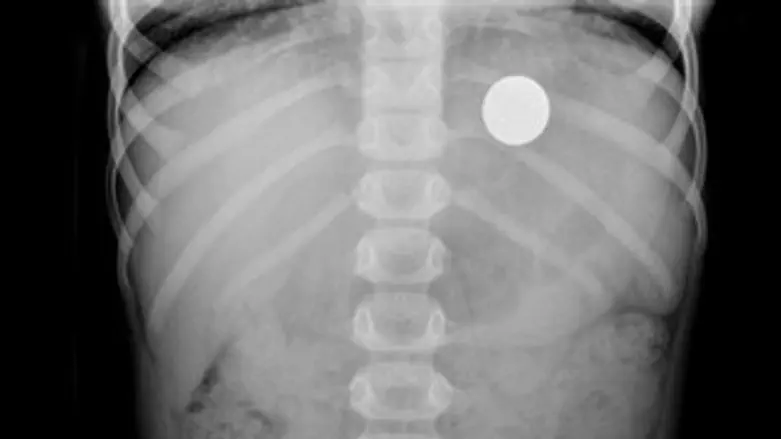

מטרת הניסוי הייתה לבדוק, האם הוא יוכל להזיז את המטבע שבפיו, בעזרת המגנט שהוצמד ללחי, אולם במהלך הפעולה, למדען הצעיר אירעה "תאונת מעבדה" והוא בלע את המטבע. למזלו של הפעוט, המטבע החליק בגרונו ונתקע בקיבתו, מבלי שזה יהווה סכנה או יכאיב לו. מיד, לאחר שבלע את המטבע, ניגש הפעוט להוריו והכריז "הניסוי כשל".

במשך שבועיים ימים המתינו הוריו של בן ה-5 ליציאתו של המטבע מגופו בדרך טבעית, כאשר הם עוקבים באמצעות סריקות אחר תנועת המטבע בקיבתו של הילד, אולם לבסוף, בעצת הרופא המטפל בקהילה, הוחלט להביא את הפעוט אתמול לבית החולים רמב"ם בכדי לסייע בהוצאת המטבע.

המטבע הוצא בטיפול שגרתי, הנקרא גסטרוסקופיה. הטיפול נעשה באמצעות הכנסת סיב אופטי עם מצלמה זעירה דרך הלוע, המאפשר את איתור המטבע ושליפתו בקלות. כמה שעות לאחר מכן, שוחרר י' לביתו, כשהוא חש בטוב.